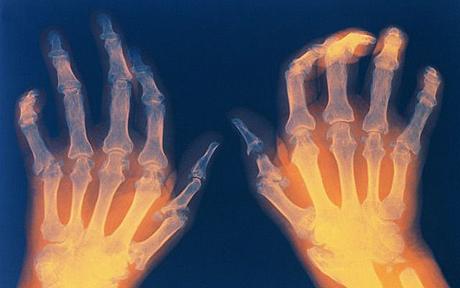

I do it all the time, about all sorts of things. Who doesn’t? It is, I think, part of the human condition to never be quite happy with the status quo. But it occurred to me this morning, as I was warming and loosening up my creaky hands – opening and closing my fingers, assessing which ones hurt in particular and where they hurt, bending and rotating my wrists – that maybe, when it comes to my RA, I’m complaining too much.

While my hands and wrists DO hurt pretty much all the time, the pain is neither overwhelming nor intense. It’s like they have headaches, the dull, background kind with the occasional drill-bit-over-the-eye type headaches. There are moments when all I can do is stop whatever I’m about and just hold my hands to my chest, massaging gently, waiting for the blaring, pulsing pain to die down. But mostly, they’re just generally sore and I manage in spite of them.

My hands and wrists seem worse than before, but how would they feel if I wasn’t taking the medicines? Would they be the same, or three times as bad? Ten times as bad? So far, I don’t have any deformity in my hands or anywhere else in my body, even though I’ve had the disease for more than two decades, and during the first, the pain it caused in various joints was both disabling and devastating. I limped frequently. The bottoms of my feet throbbed and ached constantly, as if someone had been beating on them with canes during the night. One day my shoulder would flare so badly that I couldn’t get dressed on my own. Another day my right hand would be so intensely painful I couldn’t hold a pen, or type. I often needed a cane, and